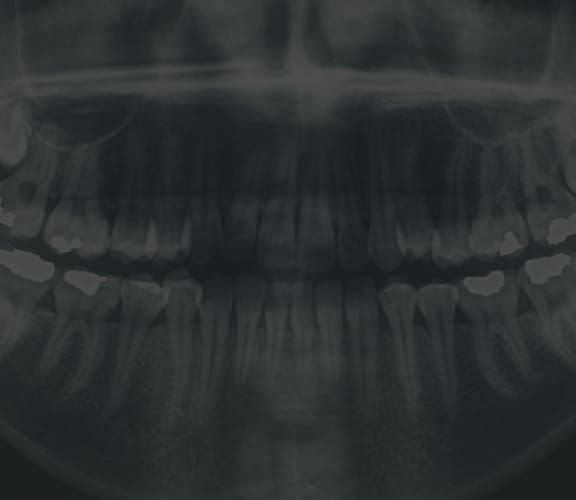

Wisdom Tooth Development

Wisdom teeth generally begin to form in your pre-teen years. By late teen years, the crown of the wisdom teeth will begin to erupt through the gums if there is adequate room. By mid twenties, your wisdom teeth will either be able to fully erupt or will have become impacted. Early removal of wisdom teeth makes the procedure easier for the patient to tolerate and promotes faster healing after wards. By your early forties, the wisdom teeth roots have become fully anchored to the jawbone and if required to be extracted, will be much harder and will need more time to heal.

Wisdom teeth also known as third molars are the last teeth to erupt into the mouth. Wisdom teeth typically appear around a person's mid-twenties but can erupt much later. If wisdom teeth don't have enough space symptoms can occur. The wisdom teeth may only partially erupt or might not come through at all. Dentists designate wisdom teeth 'impacted' if they are wholly or partly blocked from eruption into the mouth. The tooth may lie at an angle and remain tipped against an adjacent tooth. Impacted wisdom teeth can cause problems like pain and swelling; The mouth could ache when stretched open wide or it may be difficult to open your mouth. Tenderness when chewing and biting may occur. Earaches may develop from the spread of pain in the mouth. Symptoms may be intermittent but can begin anytime without warning. If you are experiencing symptoms, it is best to get treatment 'usually removal' as soon as you can to avoid potentially expensive and painful complications.